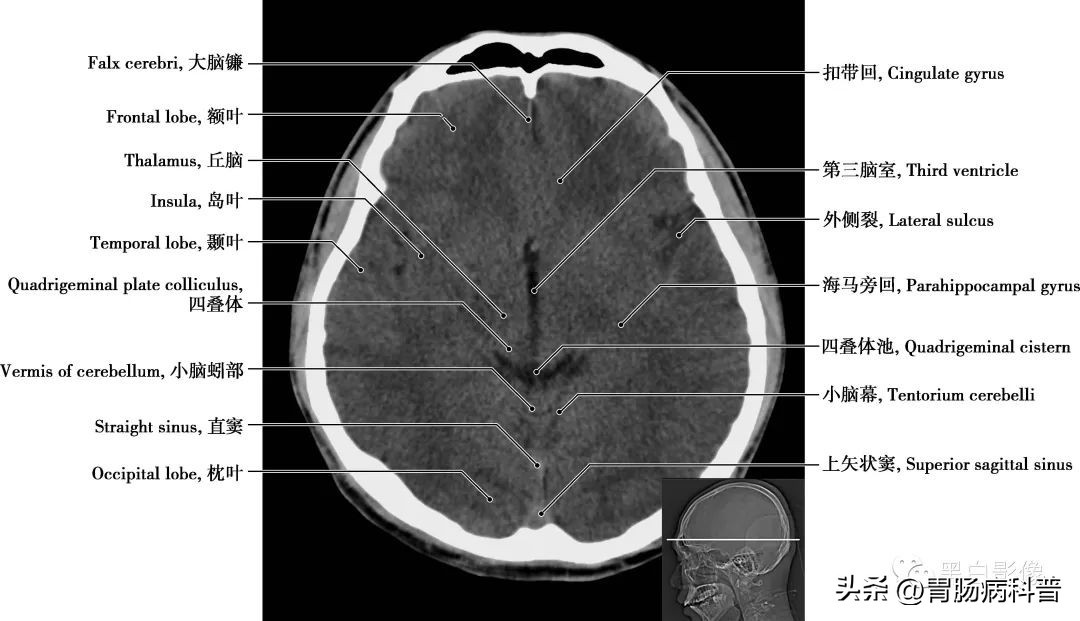

图1-1-10 经第三脑室轴位切面

第三脑室 位于间脑中央,为两侧丘脑和下丘脑之间的矢状窄隙,前方借室间孔与侧脑室相通,后方与第四脑室相通。丘脑 为间脑最大的卵圆形灰质核团,位于第三脑室两侧,左、右丘脑借灰质团块相连,其被“丫”形白质板分成前、内侧和外侧三大核群。受损时,对侧偏身感觉减退,对侧动作性震颤或偏身共济失调伴舞蹈徐动症,情绪不稳等